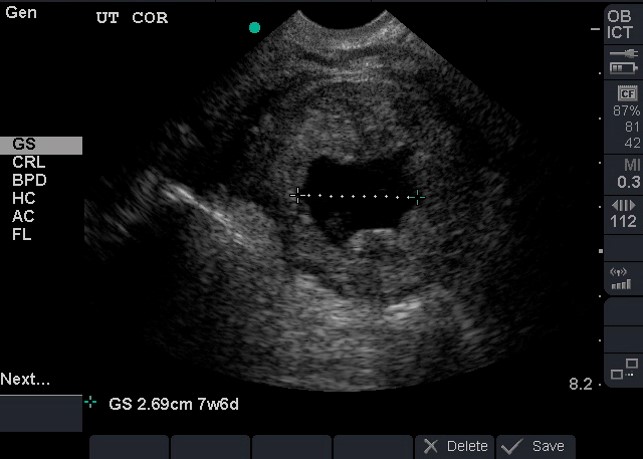

- Prior to the develop of a YS, a gestation sac (GS) becomes visible in weeks 4-5.

- Be careful not to rely on a GS as an IUP, 10-20% of ectopic pregnancies have pseudo-gestational sacs.8 (Video 8)

- A Fetal Pole develops weeks 6-7 and a heart rate is visible in the same time frame (Illustration 9, Video 9)

- Dating can be achieved by obtaining crown rump length when fetal pole becomes visible and then biparietal diameter when fetal skull becomes evident at the end of the first trimester.1 (Illustration 10, 11)